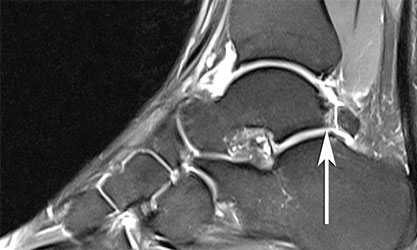

Если рентгенография не позволяет выявить патологии, это не значит что её нет. Костные разрастания могут просто не попасть в выполненную проекцию, а мягкотканные повреждения на рентгенографии не определяются. МРТ в подобных ситуациях позволяет не только локализовать повреждение, но также определить наличие сопутствующих изменений суставного хряща, связок, синовиальной оболочки, капсулы сустава, степень выраженности субхондрального склероза и формирование кист, что позволяет более точно планировать оперативное вмешательство.

МРТ того же пациента позволяющая не только увидеть и локализовать место расположение остеофита, но также показывающая утолщение суставной капсулы, отёк костного мозга - свидетельствующие о наличии большеберцово-таранного импинджмента.